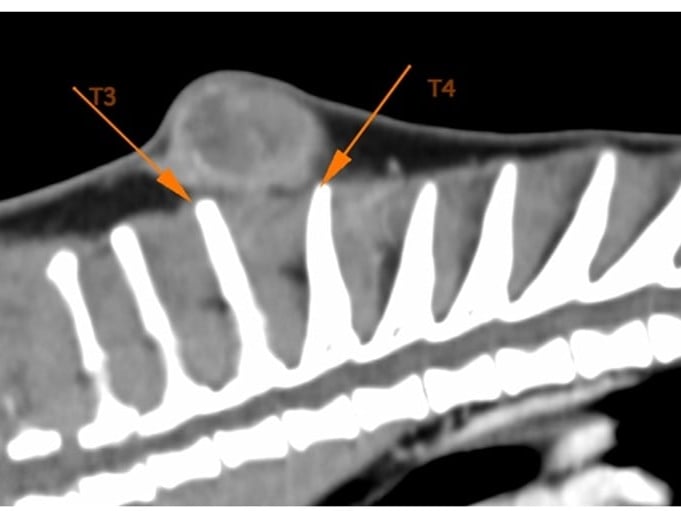

Om de diagnose met zekerheid te bevestigen werden biopten genomen, en om mogelijke metastasen uit te sluiten en de uitgebreidheid van de tumor in beeld te brengen werd een CT-scan uitgevoerd.

Op basis van de CT-beelden werden de chirurgische marges bepaald: de tumor werd ruim verwijderd met 5cm perifere huidmarges, 5 spinaal uitsteeksels en een partiële scapulectomie van het linker schouderblad. Aangezien de chip mee verwijderd werd met de tumor diende er ook een nieuwe chip geplaatst te worden, buiten het operatieveld.

Beelden van de preoperatieve CT-scan. Op basis van deze scan konden de chirurgische marges nauwkeurig gepland worden.